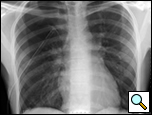

Patients who have had a second episode of spontaneous pneumothorax are those most likely to be considered for thoracoscopic pleurectomy and apical blebectomy. However, patients with a first episode of spontaneous pneumothorax who have a prolonged air leak (greater than 72 hours), incomplete expansion of the lung (Figure 1), bilateral pneumothoraces, associated hemothorax, tension pneumothorax (Figure 2), or a bleb on their CT scan (Figure 3) should be offered surgery at the time of the first occurrence [1]. Patients who have had a spontaneous pneumothorax and whose occupation places them at risk for a second episode or places them in a situation where medical intervention is not readily accessible should be considered for surgery. Therefore divers, pilots, submarine personnel, and those that work or live in the wilderness or space are suitable patients [1].

| Figure 1: Chest x-ray showing incomplete expansion of lung after chest tube placement. | Figure 2: Chest x-ray showing tension pneumothorax with mediastinal shift. | Figure 3: CT Scan showing apical bleb. |